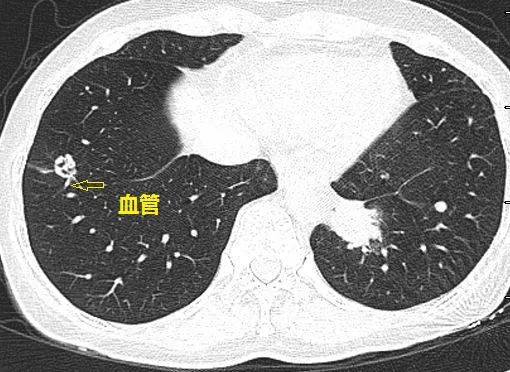

血管结节

穿过肺结节的血管其实是一个纸老虎

双血管不同方向 ,扎入磨玻璃结节